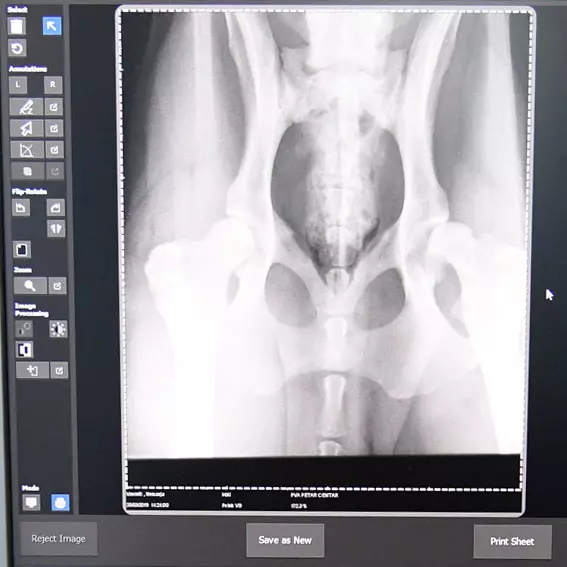

Radimo rendgensku dijagnostiku u maloj praksi i vršimo izdavanje sertifikata za kukove i laktove pasa.

Dodali bismo i to da se bavimo najpreciznijom rendgenskom dijagnostikom, jer pored velike stručnosti koju posedujemo, koristimo i najsavremeniju opremu.